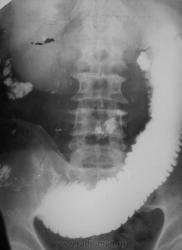

При исследовании ЖКТ -эктазия желудка и первых петель тонкой кишки, далее контрастное вещество не пошло.

Снимки через 24 и 36 часов

Надо подумать о препятствии в илео-цекальной области.

Спайка в илеоцекальной области, сдавливающая тонкую кишку косо-поперек.

Это зктазированы первые 50 см "тощей" кишки!

Так не против же "тощей", но проекционно препятсвие где?

Давит сегодняшняя "глистная инвазия", ну прямо давит, да еще и "крапочки" какие-то на левом снимке справа на уровне Л2, Л3.

Проходимость мизерная... практически полный стеноз...

Высокая тоно-кишечная вероятно обутрационная непроходимость. Причин может быть много. Например безоар,желчный камень,клубок аскарид,опухоль, штранг в сальнике,аномалии развития и тд.

На операции редкая локализация аденокарциномы тощей кишки, 50-60 см от связки Трейца, полное сужение провета. Резекция фрагмента кишки. Видимых метастазов не было, отдаленный результат не знаю...